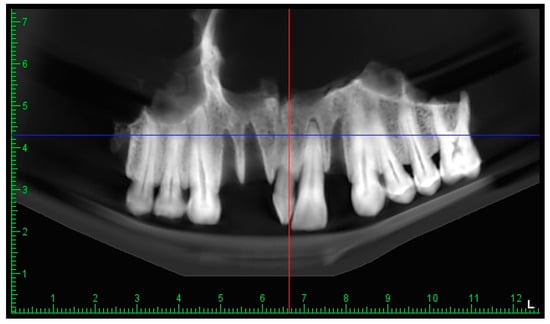

3.3. The CBCT Scan

4.3. The Role of CBCT in Paleoimaging